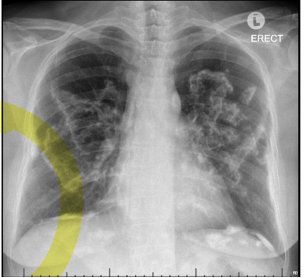

- Chest X-ray often indistinct can look like a lot of different things, could look like pneumonia, different types of infiltrates could also be normal

c. Dx: CXR small rounded opacities bilaterally and calcified hilar lymphadenopathy bilaterally (eggshell calcification) UPPER LOBES

o Imaging: bilateral hilar adenopathy